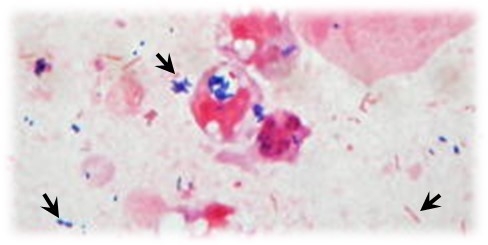

細菌は下記の画像のように染色され、青色やピンク色に染まります。

こちらは肺炎を引き起こす代表的な細菌、肺炎球菌のグラム染色像です。

肺炎球菌は菌が2つ連なっており、よく見ると菌の周りが白く抜けて見えます。

これは菌の周りに莢膜(きょうまく)があり、その部分は染まらないことが特徴です。

これらの特徴などから肺炎球菌と推定することができます。

こういった細菌ごとの特徴を観察することで菌種を推定しています。